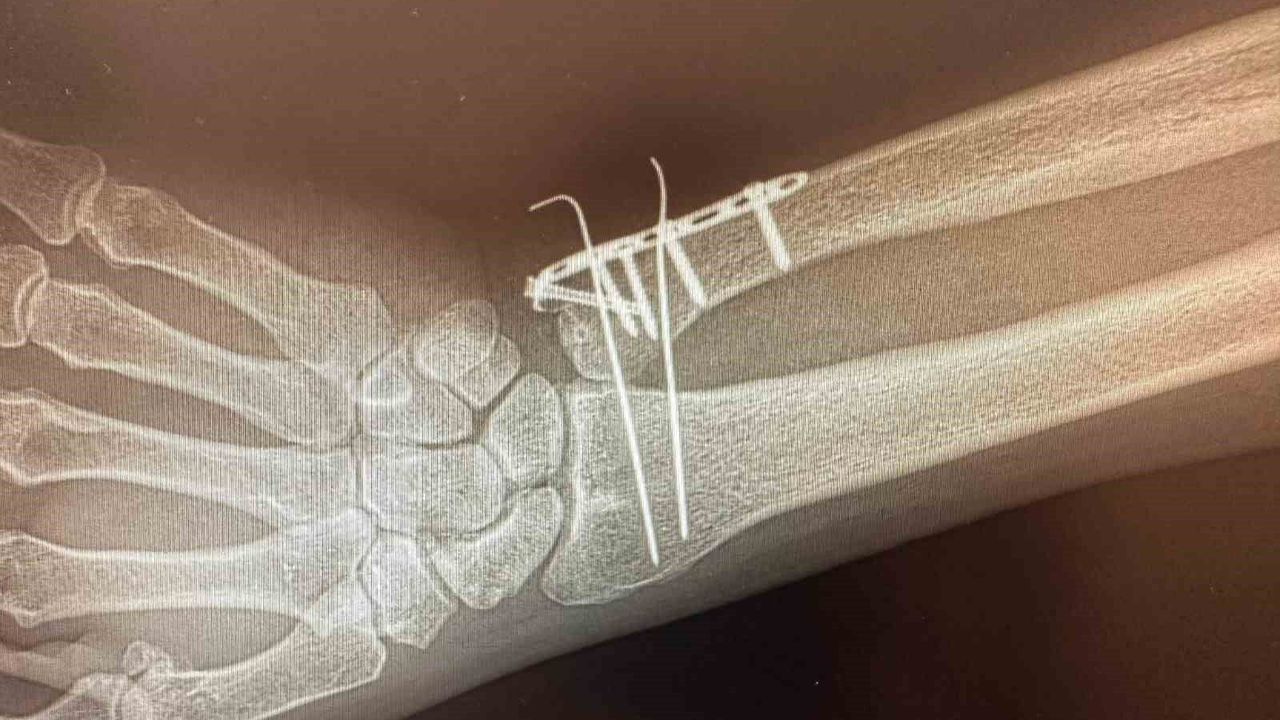

C Kollu Skopinin ameliyathane ortamında hastanın iç yapısını anlık ve hareketli olarak görüntüleyen, X-ray tabanlı taşınabilir bir röntgen cihazı olduğu bildirildi. C şeklindeki yapısı sayesinde her açıdan görüntü alabilen cihazın özellikle ortopedi, travmatoloji, beyin cerrahisi, üroloji ve kardiyoloji işlemlerinde yüksek çözünürlüklü görüntü sağlayarak müdahalelerin daha güvenli ve hızlı yapılmasına imkan tanıdığını aktarıldı.

Cihazın özellikle kırıkların düzeltilmesi, vida ve plak uygulamaları, kalça ve diz protez ameliyatları gibi ortopedi ve travmatoloji işlemlerinde etkin şekilde kullanılacağı ifade edildi.